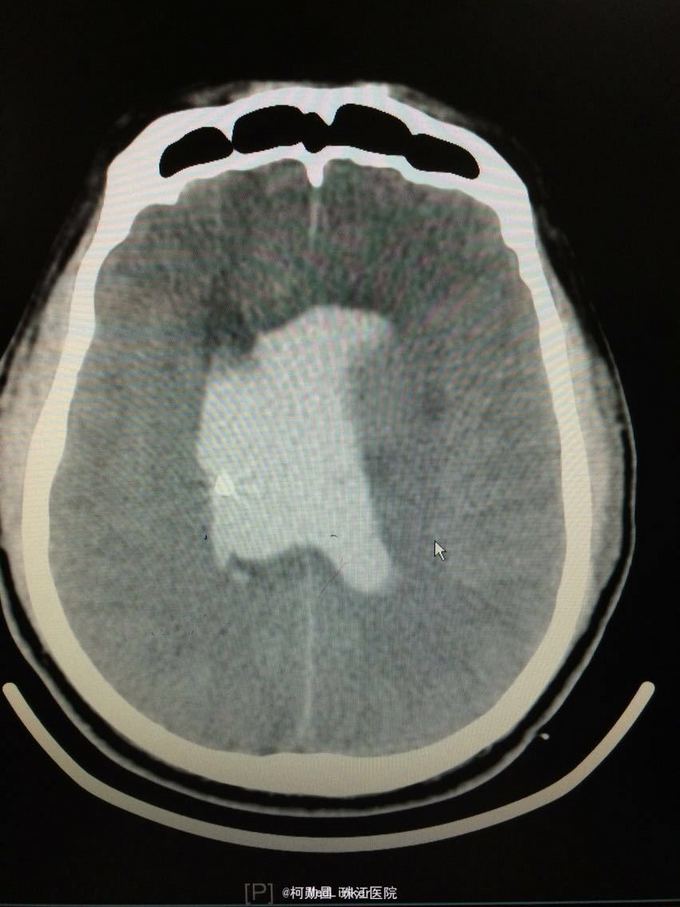

主诉:突发意识障碍4小时 病史:患者57岁男性,入院前一天晚上突发意识不清,伴呕吐胃内容物多次,无肢体抽搐等,随即由家人呼叫120送至我院,急诊行头颅CT提示左侧基底节区出血破入脑室。既往高血压病史10多年

查体:神志不清,双侧瞳孔散大,对光反射消失,四肢肌张力正常,肌力无法检查 辅助检查:头颅CT提示左侧基底节区出血破入脑室

诊断:左侧基底节区出血并破入脑室 处理:急诊行侧脑室钻孔外引流术,术后并予积极抢救,最终抢救无效死亡

随访:患者最终死亡。 讨论:该患者属于典型的高血压性脑出血,且出血量多,预后不良。壳核和丘脑是高血压性脑出血的两个最常见部位。典型可见三偏体征(病灶对侧偏瘫、偏身感觉缺失和偏盲等),大量出血可出现意识障碍,也可穿破脑组织进入脑室,出现血性CSF,直接穿破皮质者不常见。